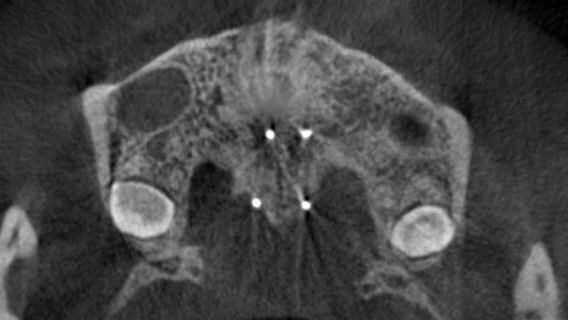

まず、MSEの中央部に正中口蓋縫合をまたぐ位置に4本の矯正用アンカーを埋入しました。浸潤麻酔で痛みなく、15分程度で処置自体は終了です。

中央部にネジを回す部分があるため、付属するレンチを患者さんに1日1回を目安に回していただきます。

初めは拡げる応力が集中するため、鈍痛を感じることもありますが、日常生活に大きな支障が出るほどではありません。

MSEの効果が出てくると、上顎の前歯部には隙間ができます。これは見た目としては我慢ポイントにはなるのですが、確実に正中口蓋縫合が離開して骨格的な拡大ができている証拠でもあるので不安になる必要はありません。

CT断面図を観ていただくと、正中口蓋縫合がしっかりと離開されています。